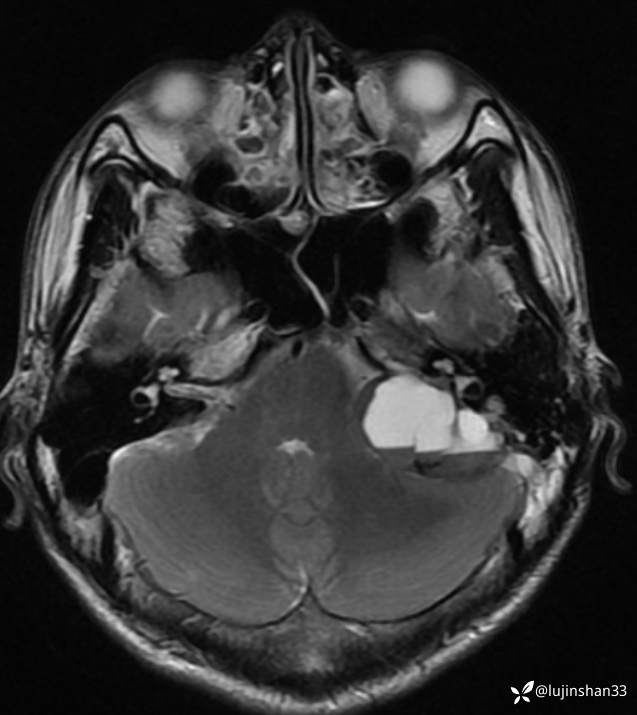

首次术前MRI

【现病史及既往史】:患者2年前无明显诱因出现左耳搏动性耳鸣、听力下降,耳鸣持续存在,伴轻度头晕,无眩晕及恶心、呕吐,无左侧外耳道流脓、流血,无视力下降,于2018-09-19在XXX市第一人民医院行颞骨CT及颅脑核磁示:左侧岩骨-桥小脑角区占位性病变,伴骨质破坏,考虑肿瘤性病变,于2019-02-19日于在我科住院行“经枕颈联合径路颞骨、颈静脉球窝及后颅窝肿瘤切除+腹部脂肪取出术腔填充+外耳道封闭”,病理结果(2019-2-19,我院)(左颞骨、左颞骨后颅窝、后颅窝硬脑膜) 富于破骨样巨细胞的肿瘤,背景为基质细胞梭形,界限不清,部分区域可见出血,局部见反应性骨形成,考虑为骨巨细胞瘤。送检瘤组织大小分别为1.2x1.2x0.7cm、7x6x2.5cm、3x2x0.8cm。(左颈部)淋巴结未见转移肿瘤(0/2)。免疫组化结果:p63(部分+),SATB2(+),Ki-67(+10%)。术后定期门诊随访,于2019-09-02行颞骨CT示:左侧颞骨骨巨细胞肿瘤术后改变,左后颅窝异常强化灶累及左侧颞骨斜坡,考虑复发,为进一步手术治疗来我院,以"颞骨骨巨细胞瘤术后(左)"收住入院。